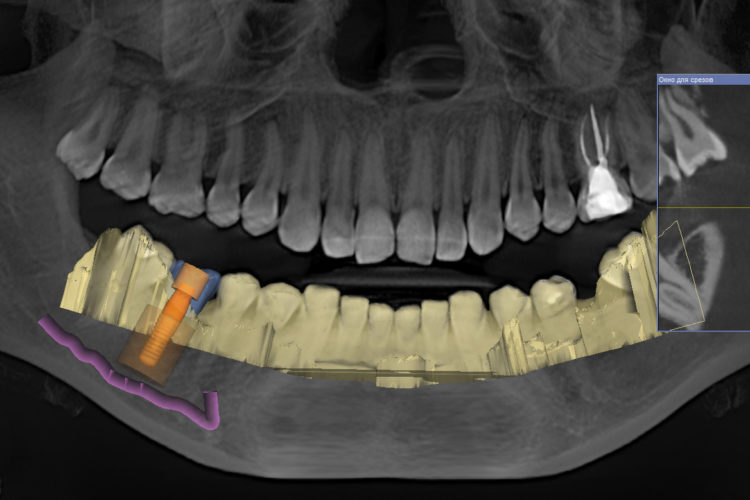

Клинический кейс имплантации

Все этапы: от компьютерной томограммы до установки коронки на имплант.

Установленный имплант: 4.5 мм на 11.5 мм

Коронка на имплант: дисиликат лития, винтовая фиксация, изготовлена в клинике за 3 часа.

Абатмент: индивидуальный титановый.

Длительность имплантации: 1.5 часа.

Промежуток от импланта до коронки: 3 месяца.

Заключение: проведена установка импланта с одновременной пластикой десны и формированием межзубных сосочков. В имплант установлен формирователь десны. Рана ушита. Швы необходимо снять через 10-14 дней. Даны рекомендации в послеоперационный период.

Установка коронки на имплант запланирована через 3 месяца.

1. Предварительно пациенту проводится компьютерная томография челюстей. Это трехмерное изображение челюстей на котором доктор оценивает тип кости, расположение важных анатомических образований (например, на нижней челюсти - это нижнечелюстной канал, в котором проходит нижнечелюстной нерв; при неправильной подобранной длине импланта зуба возможно повреждение нерва и нарушение чувствительности половины нижней челюсти и языка).

В специальной программе мы подбираем оптимальный размер импланта: его длину и диаметр. Диаметр импланта подбирается с учетом ширины альвеолярного отростка (участка кости, куда будет установлен имплант). После анализа полученных данных мы предлагаем пациенту возможные варианты системы имплантов различной стоимости, с описанием их преимуществ и недостатков. Процент приживаемости достаточно высокий у всех систем, однако у имплантов Штрауман и Нобель этот показатель самый высокий, а вероятность отторжения наиболее низкая.

2. Виртуальная установка выбранного импланта в челюсти. В программе планирования имплантации мы выбираем в каталоге необходимого производителя имплантов, тип импланта, а также его длину и диаметр. Затем располагаем его в костной ткани челюсти и повторно проверяем расположение относительно рядом стоящих зубов и анатомических образований. В сложных клинических ситуациях дополнительно проводится виртуальное протезирование. Например, при восстановлении зубов на беззубых челюстях - предварительное планирование будущего протеза очень важно и позволяет разместить импланты в челюсти таким образом, чтобы обеспечить равномерное распределение жевательного давления и высокий эстетический показатель.

Важно: чтобы поставить имплант зуба необходимо 3D изображение челюсти; планирование имплантации не проводится по двухмерным изображения (по обычному рентген снимку), так как они не позволяют оценить необходимые показатели: ширину и высоту костной ткани.